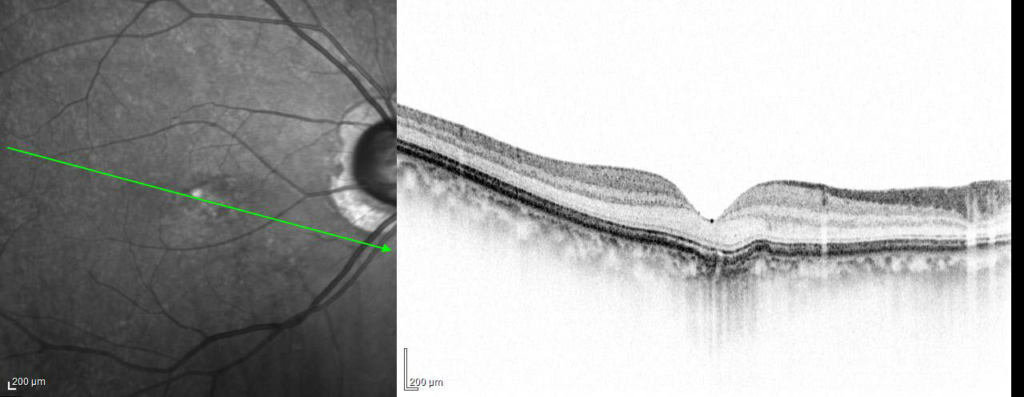

2022/1